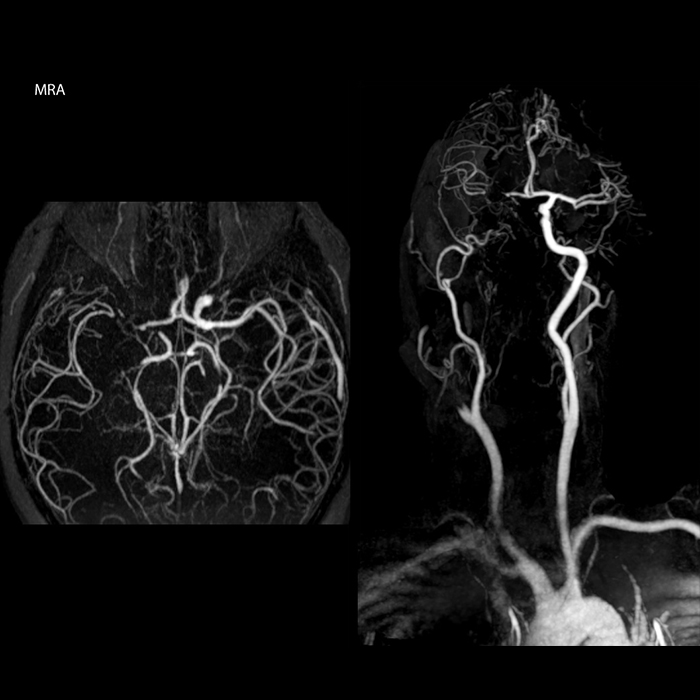

Every minute counts in stroke imaging

“In France, stroke is usually imaged with MRI, not CT, even for emergency treatment. This is because MRI helps us directly visualize ischemia in the acute phase, but can also help rule out differentials such as MS and hematoma. In addition, we can assess the intracranial and extracranial vessels during the same examination,” says Dr. Savatovsky.

The first challenge in MRI of stroke is speed. The patient typically arrives from an ambulance in the MRI preparation room and the installation is done on a separate dock outside the scanner room. “The venous access is placed during the neurological examination. If the delay from the first symptoms allows the patient to receive thrombolysis we do a very fast examination that typically lasts about 11 minutes including the pre-scans. In the case of transient ischemic stroke we usually add ASL perfusion because in some symptoms with negative diffusion, ASL sometimes indicates a vascular origin.”

“Ingenia provides great flexibility in the parameters setting. We can tune a sequence the way we want,” says Dr. Savatovsky. “For example, in a stroke exam we use a FLAIR sequence of about two minutes instead of the four-minute FLAIR we use for MS. The diffusion is 30 seconds, the T2*-weighted scan is 30 seconds, the angiography scan time is less than one minute. Ingenia is a great scanner in that situation; even with these fast sequences we can achieve good images with good SNR. When the first sequence tells us that it’s not an ischemic stroke but a hemorrhagic stroke, we may switch to a time-resolved angiography to look for vascular malformations and venous thrombosis.

The ideal stroke protocol?

“Every center is different, but for me the ideal protocol for stroke includes diffusion weighted imaging, FLAIR, and fast susceptibility imaging,” says Dr. Savatovsky. “Our fast susceptibility weighted imaging takes 50 seconds, so it’s as fast as T2*-weighted imaging. It visualizes hemorrhage but also the clots. We also do 3D MR angiography that provides information on cervical and brain vessels. If the patient does not need immediate treatment, or if additional information is needed to decide on treatment, we might also add perfusion imaging and post-contrast T1-weighted imaging.”